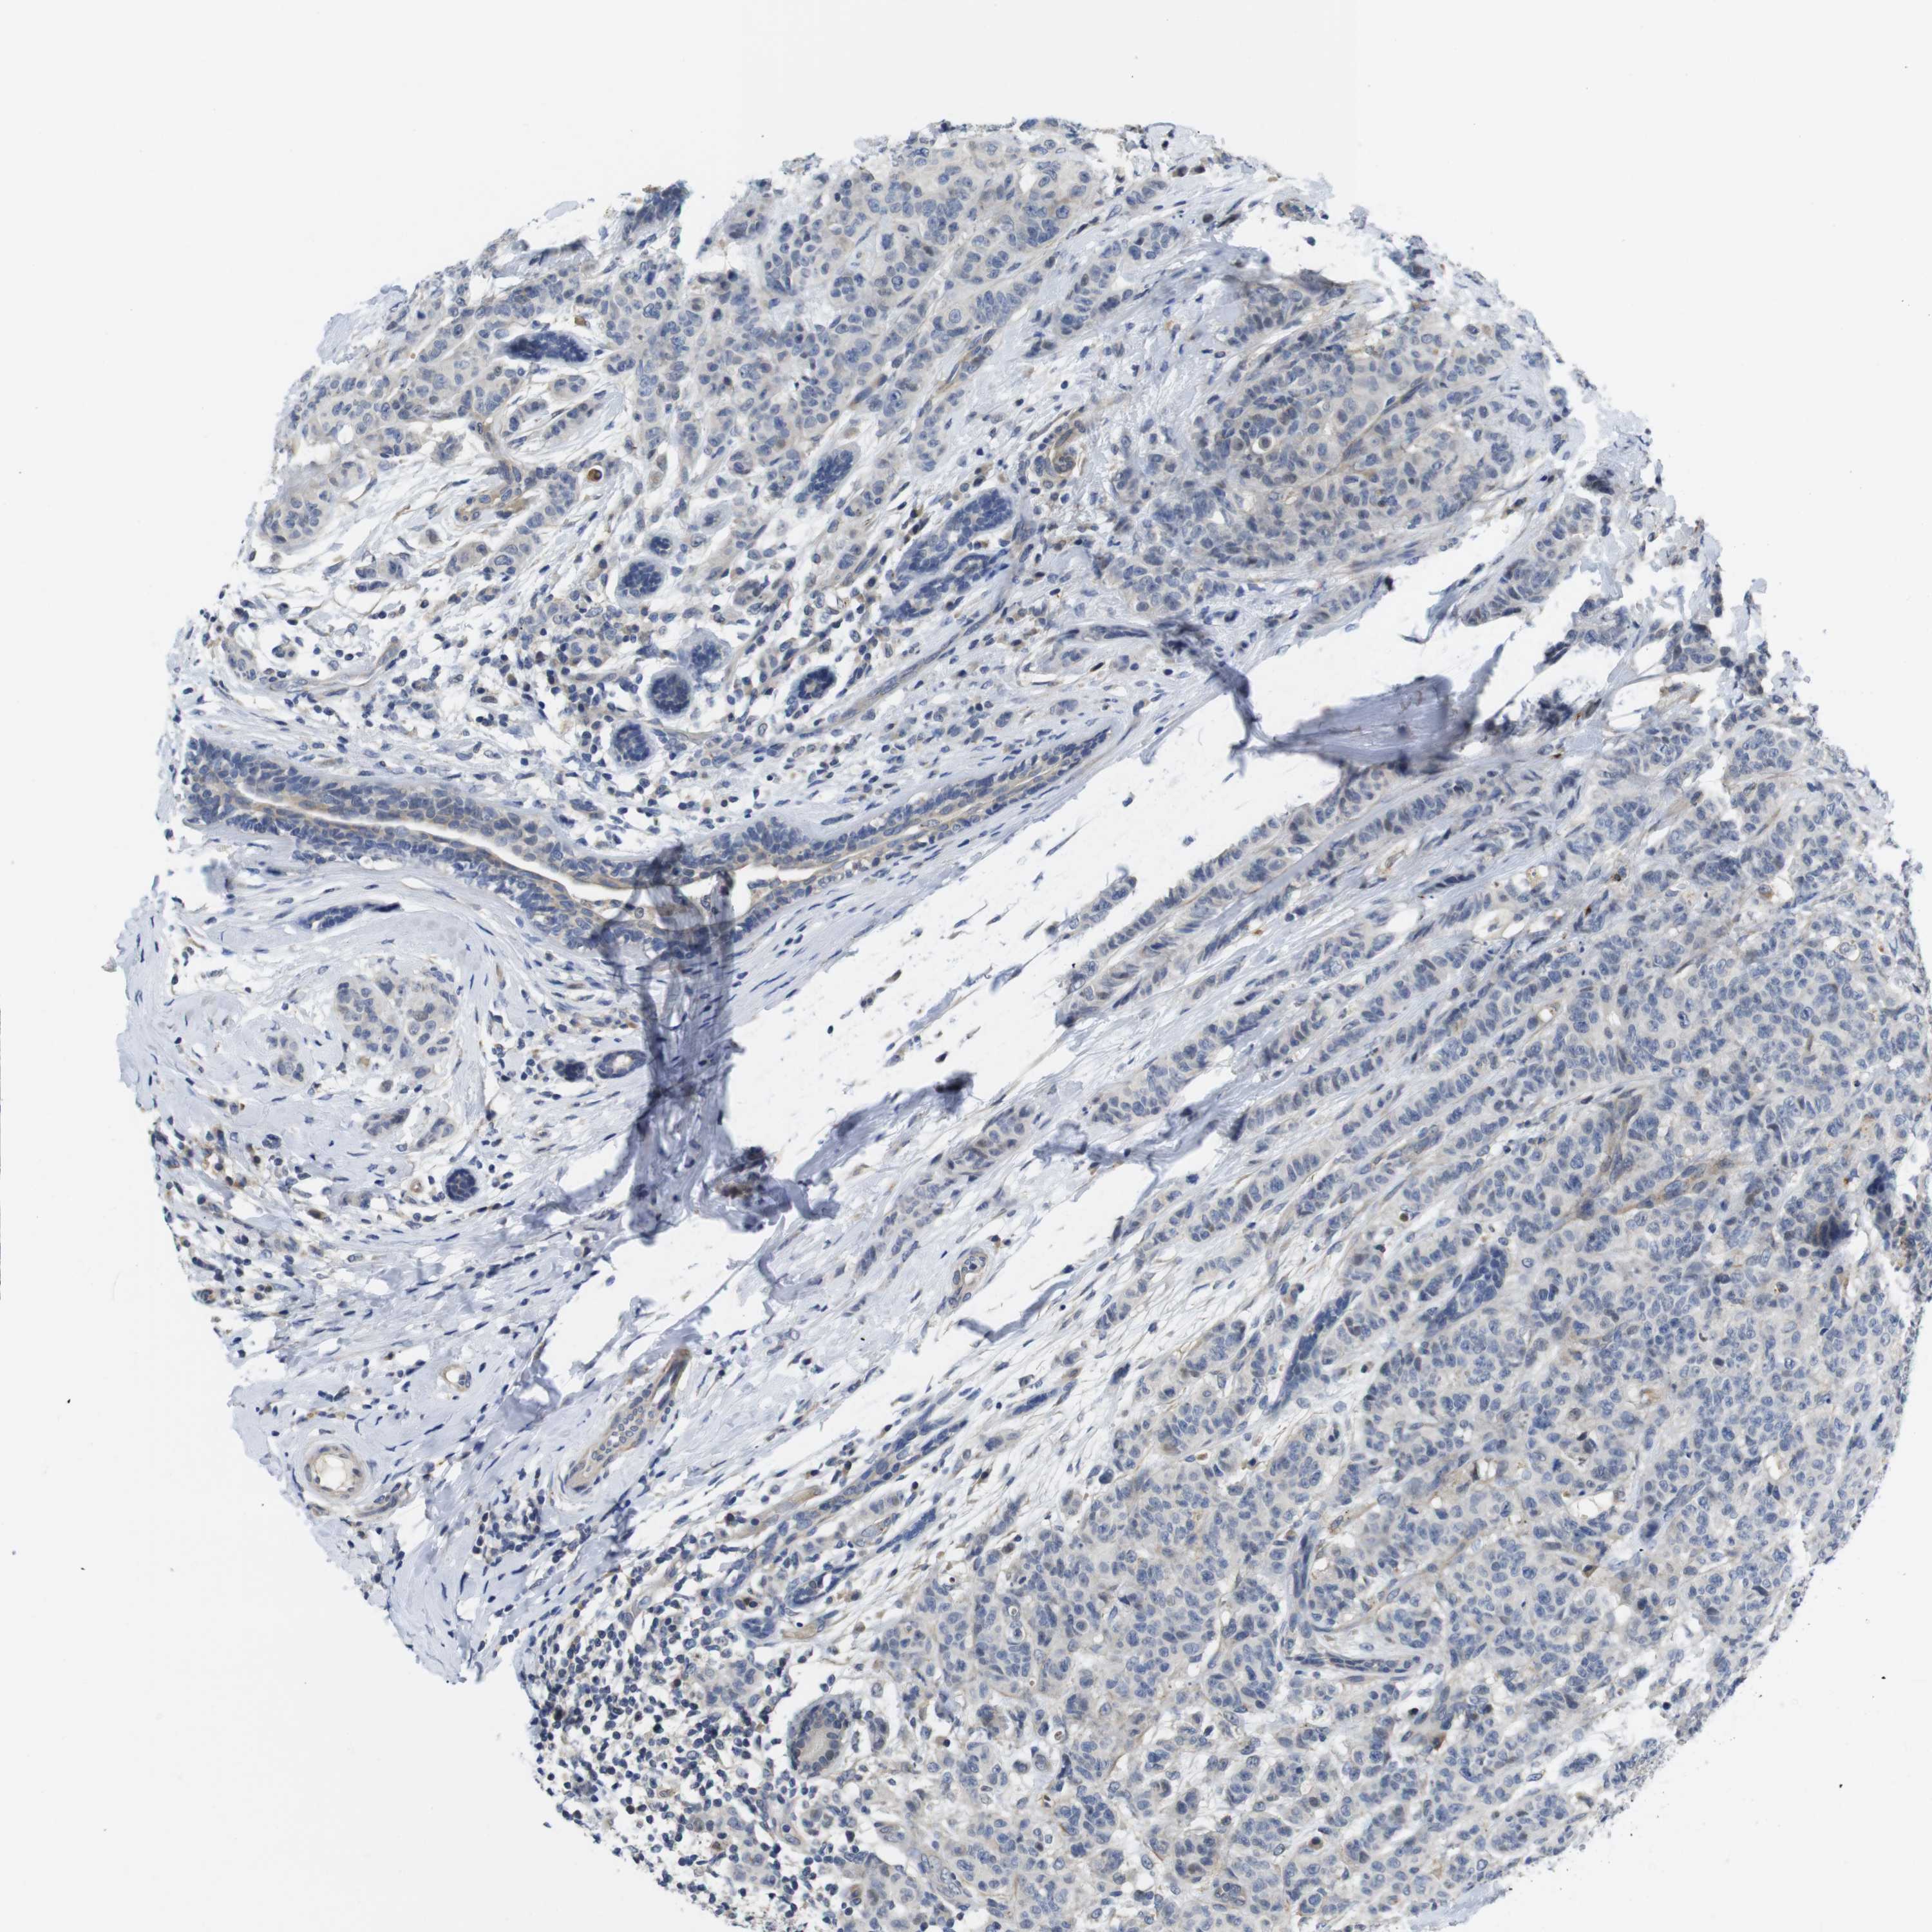

CANCER BREAST CANCER Show tissue menu

BRCA TCGA BRCA VALIDATION PROTEIN EXPRESSION